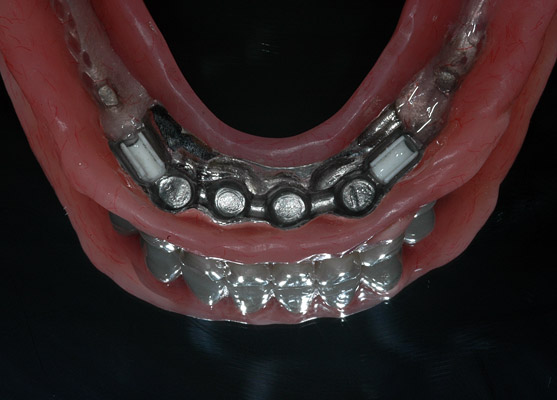

Chirurgie et implantologie

4 implants mandibulaires, barre et appareil complet